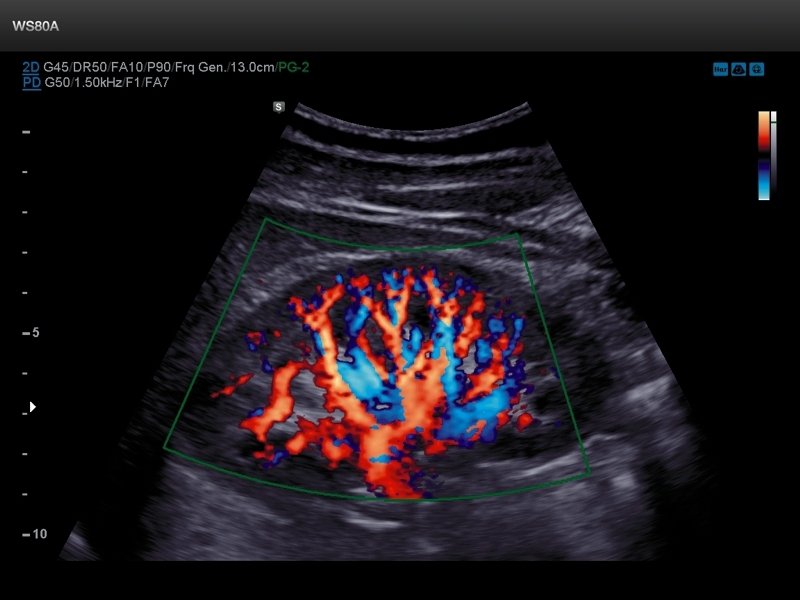

[RU] Ultrasound image №663: Renal flow in S-Flow™ mode.

Echogramm was received by ultrasound scanner WS80 (out of production).